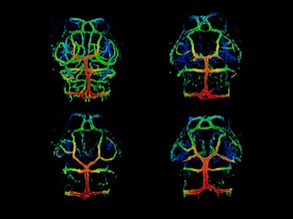

Bright Blood

03